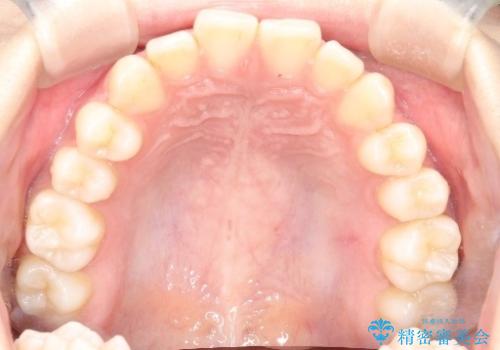

初診時の歯並びの状態としては、上下前歯が噛んでいない開口という状態であり、前歯を中心に上下とも歯の間に隙間がある状態でした。

また、開口、スキッ歯の根本的な原因として考えられる、舌突出癖による後戻りの防止のためにMFTという舌のトレーニングも行いました。